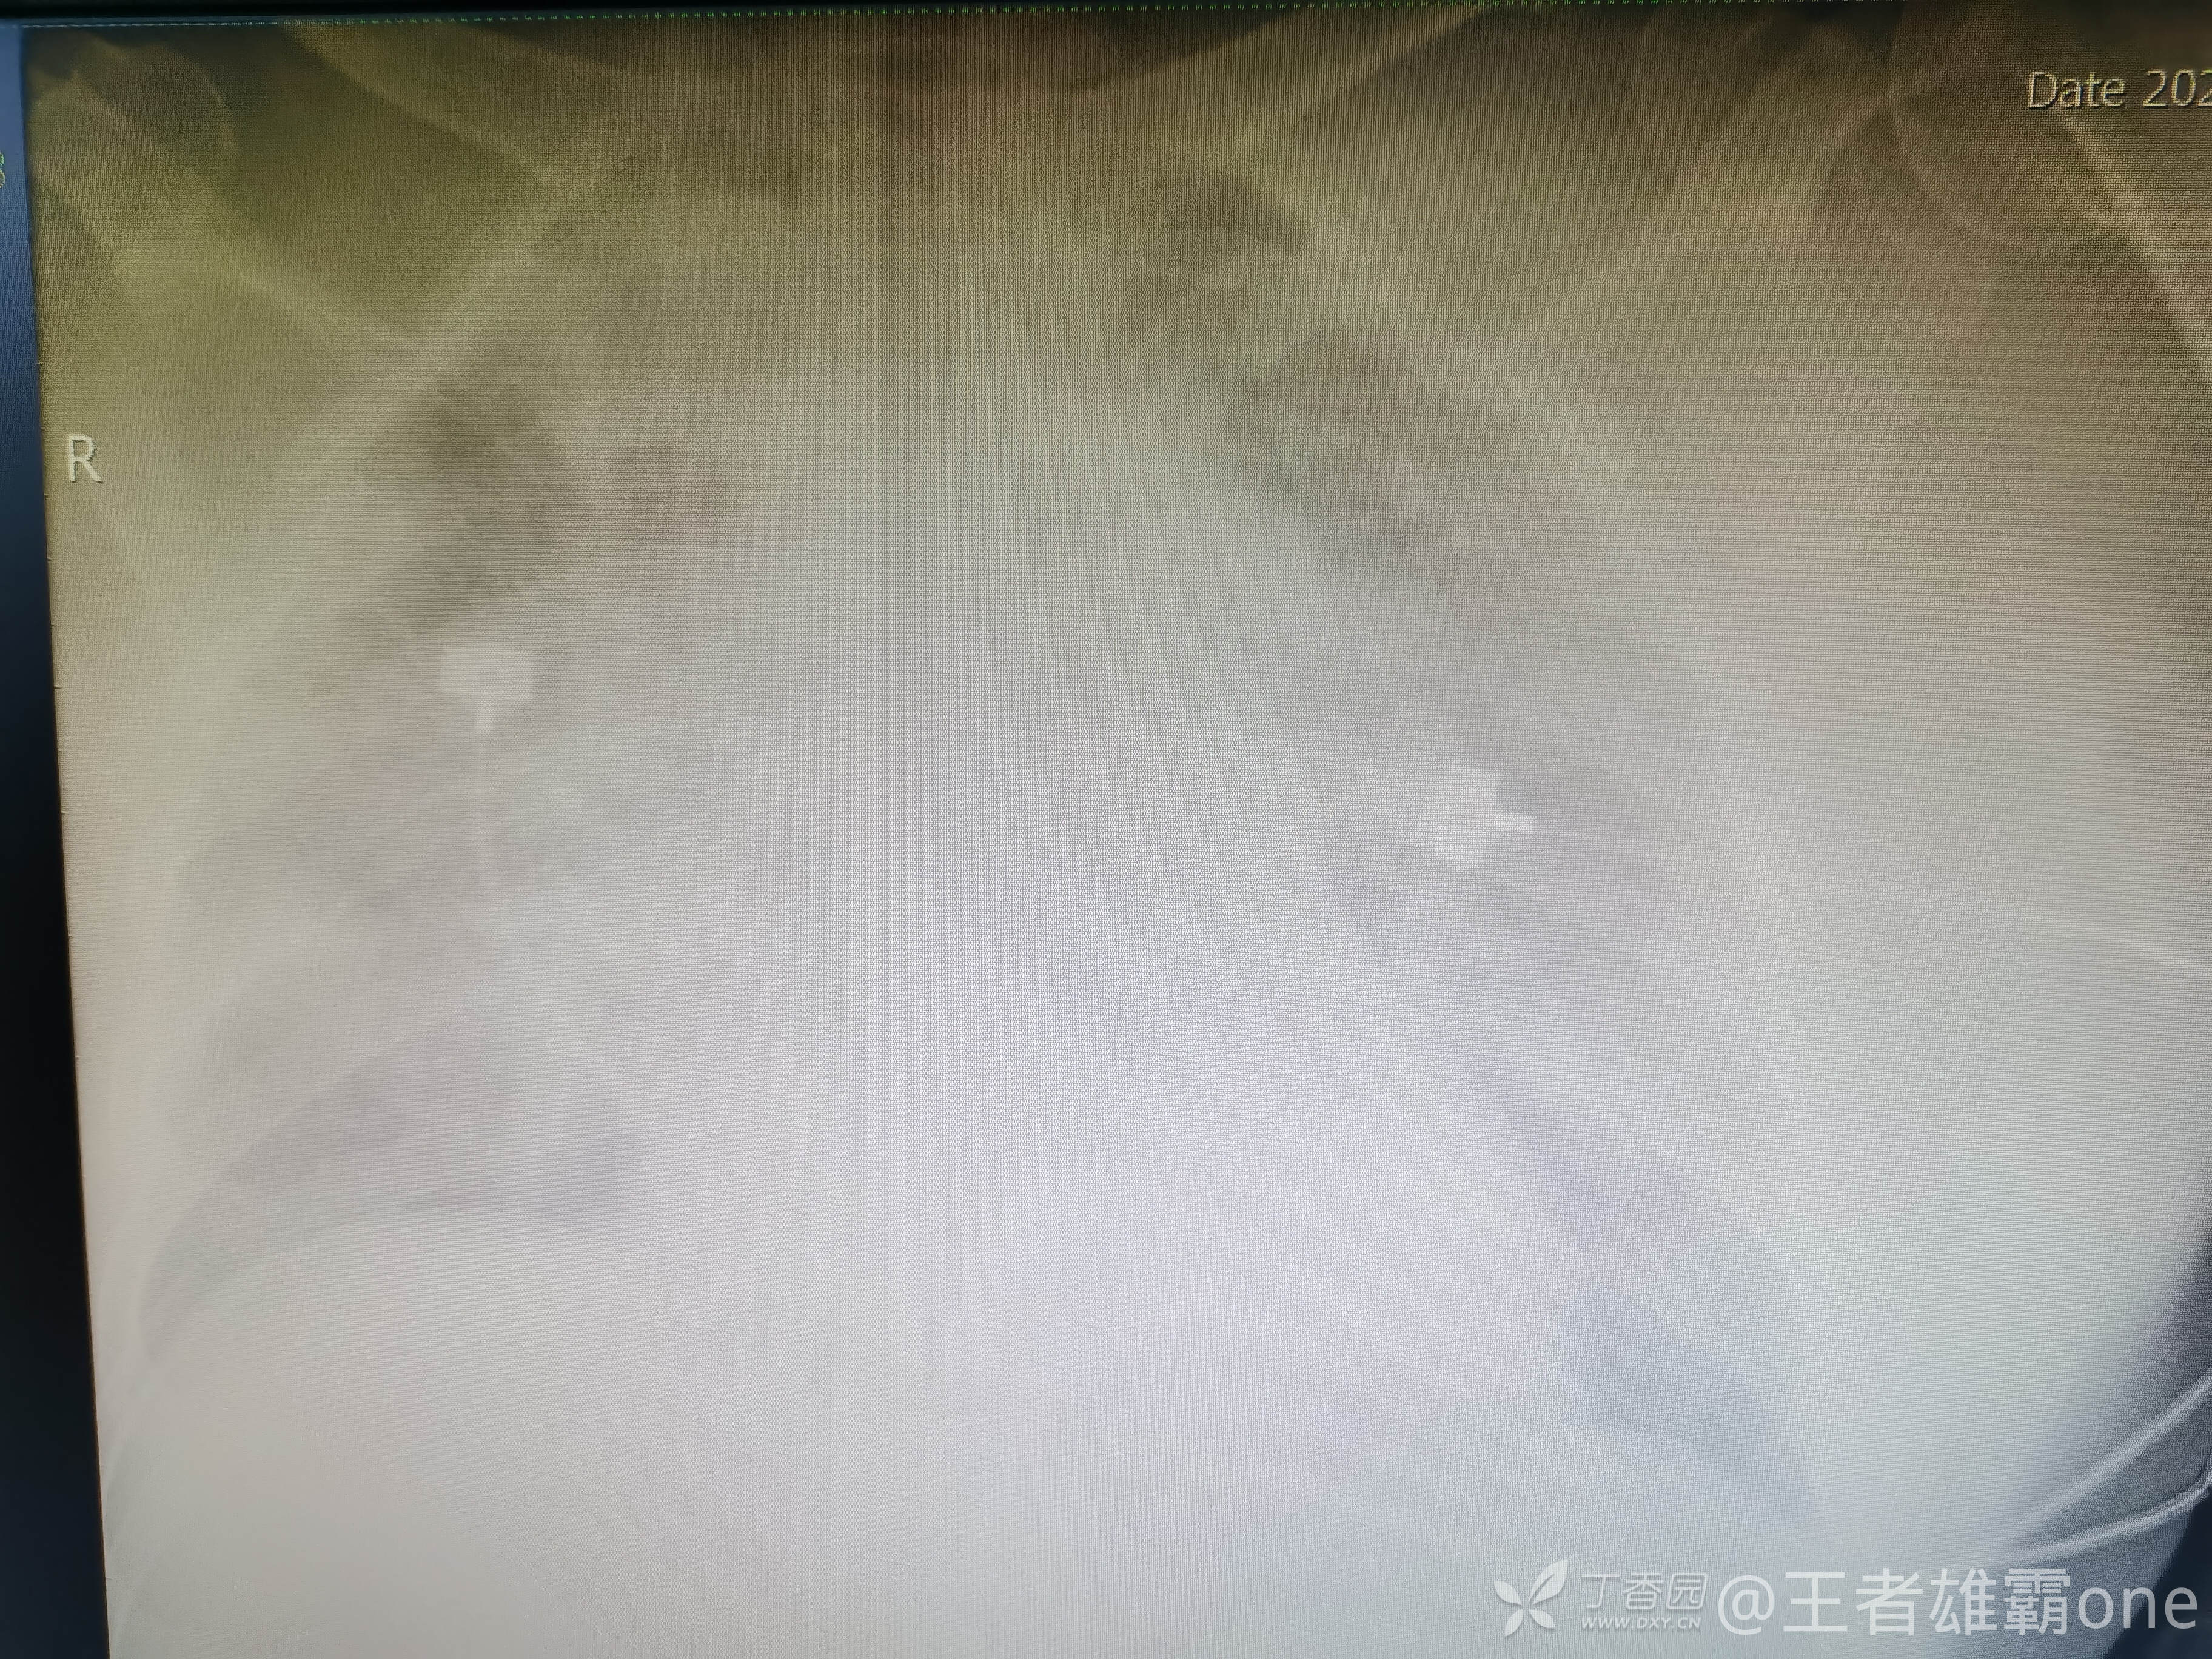

收入院治疗期间,患者神志清晰,体温、血压、心率等生命体征基本正常,到了凌晨02 :00左右出现呼吸明显急促(呼吸频率30次/分以上),改面罩高浓度吸氧,血气提示氧分压57mmHg,二氧化碳分压37mmHg,乳酸4.4mmol/L,血红蛋白10.4g/dL。查急诊胸片:

给予气管插管呼吸机通气。。